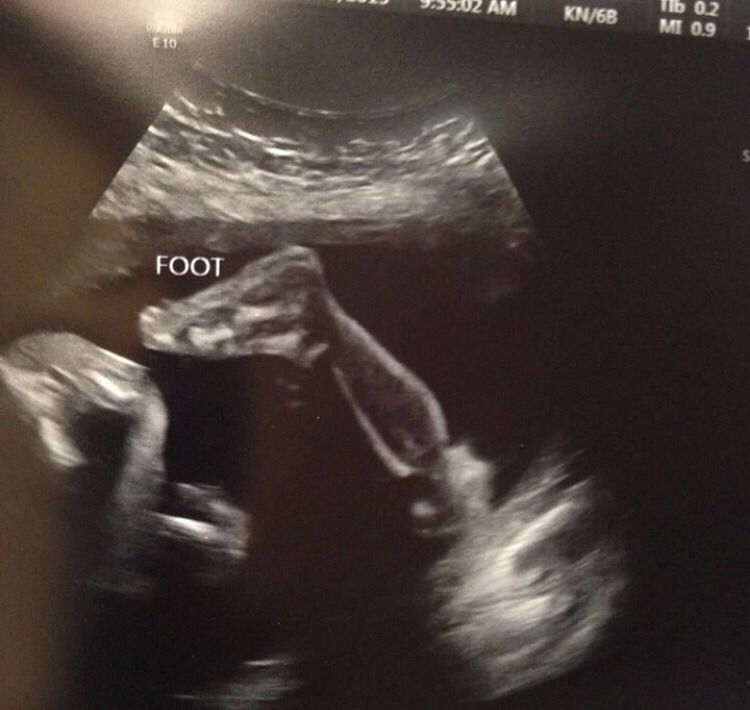

We walk inside, wait a while, finally see the doctor. He then proceeds with the ultrasound and we let him know that we wanted to know the baby’s gender. As soon as the monitor went on my belly… it was clear as day.. a boy part! We both just laughed so hard as soon as the doctor confirmed what we thought we saw! Brandon’s exact words were “we are having a little dude!” I couldn’t believe it! I was so excited! And after all of that fear and worry about this, such a sweet result! My heart was happy! It’s like all of a sudden, this sweet baby had an identity and we could prepare and be excited about this baby! We left the hospital and went home to surprise friends and family with a little scavenger hunt! Everyone was so excited and I think a bit nervous that maybe I was sad. I don’t think it had taken very long for everyone to see that I was quite alright.